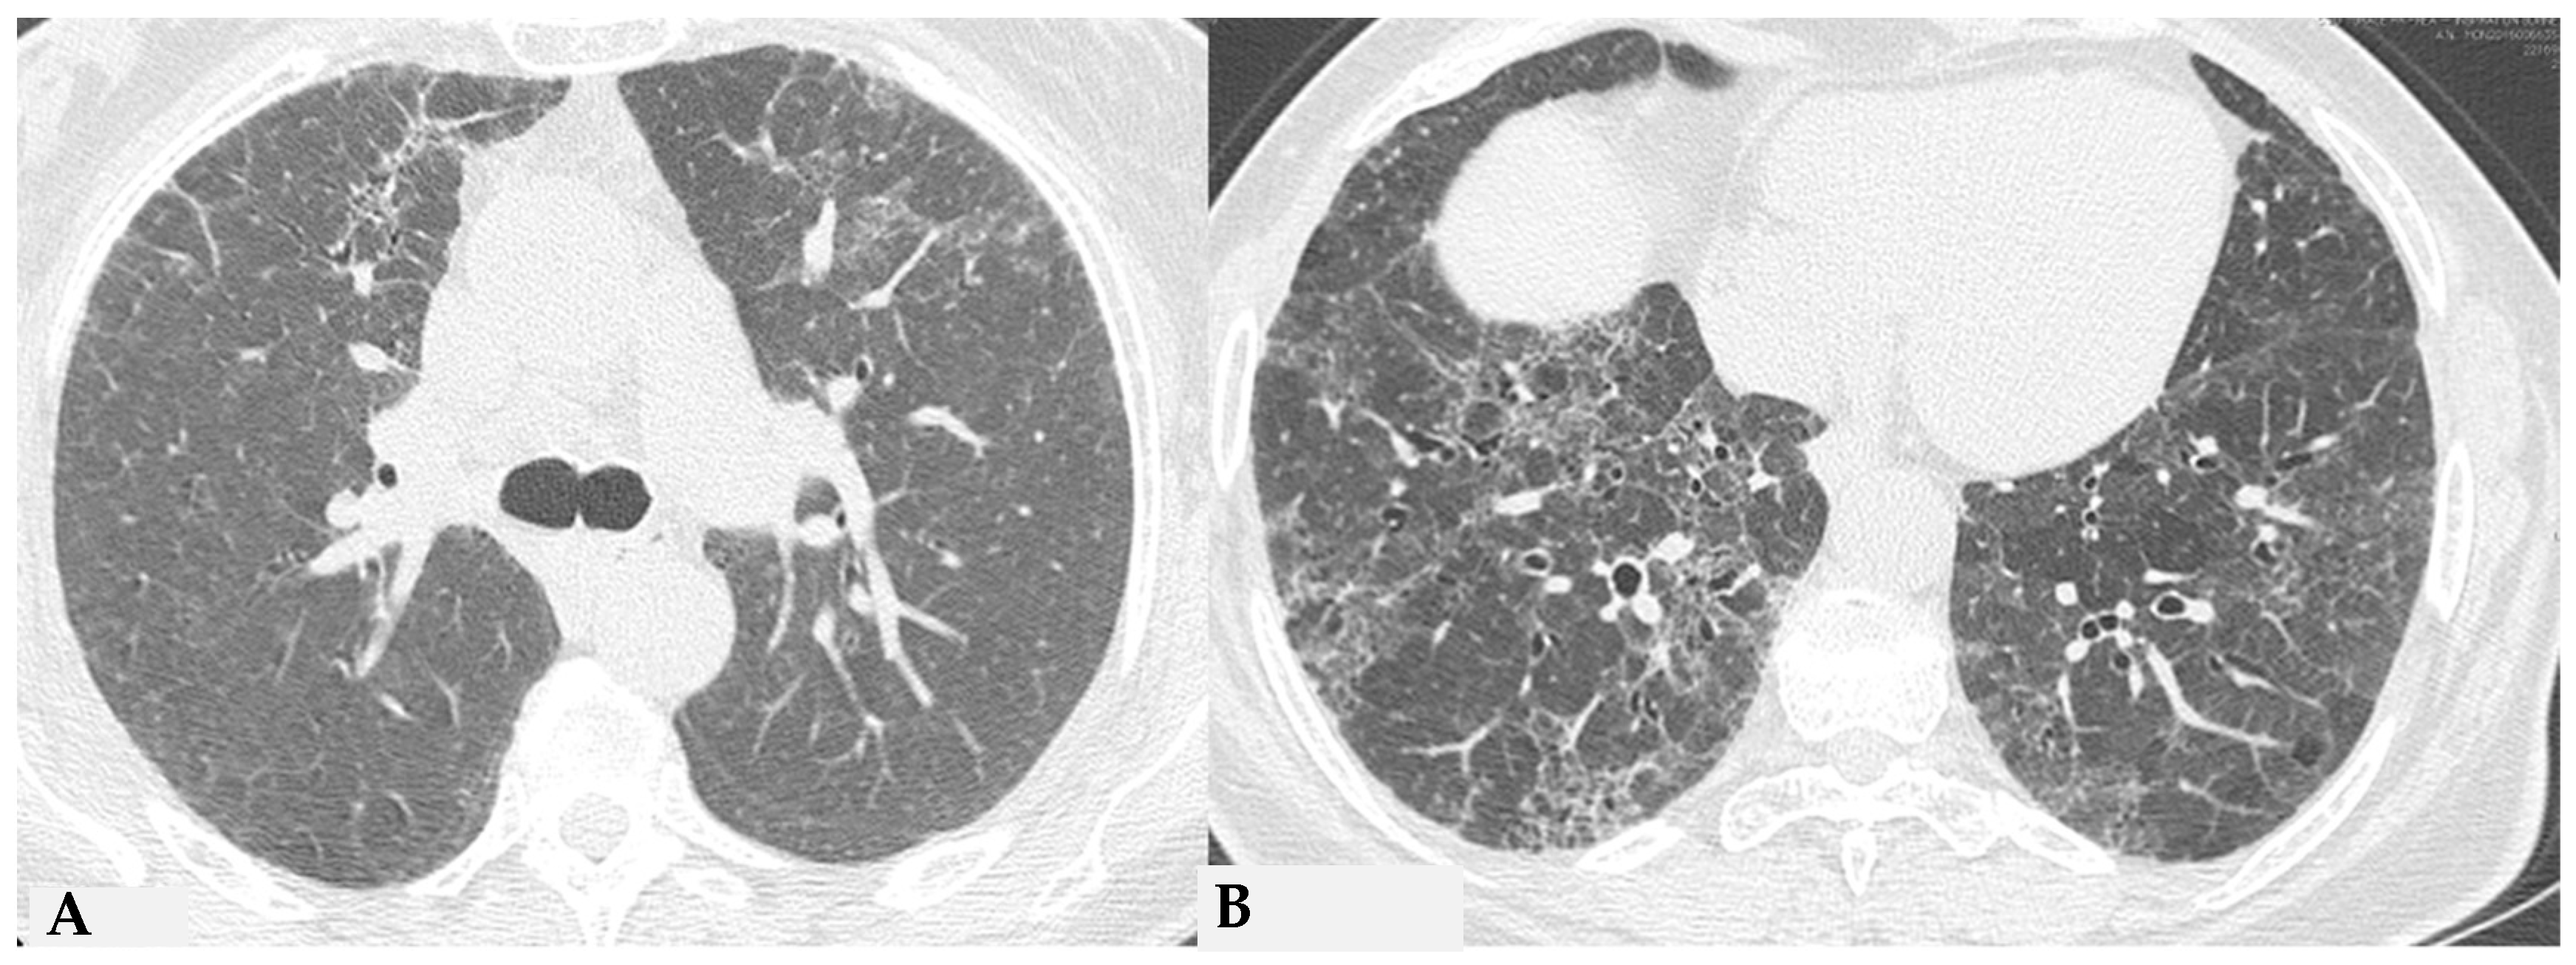

Due to intrinsic limitations in spatial resolution and contrast, chest X-rays are ineffective in evaluating NFHP, as they may appear normal or demonstrate nonspecific reticular changes in advanced forms. In cases of clinical suspicion, HRCT is considered the gold standard for detecting HP-related alterations. A rigorous methodological approach is required for HRCT to enhance mosaic attenuation areas, which can be accurately diagnosed as “air trapping” in expiratory scans, with a well-known algorithm in the literature: 1/1.25 mm thickness, specific high-resolution convolution kernels and reconstruction filters (bone filters added to soft tissue filters for accurate mediastinal evaluation and assessment of additional ancillary findings) and volumetric acquisition in the inspiratory and expiratory phases (low dose, if necessary). This evaluation plays a key role in diagnosing HP and identifying components that can affect the lungs differently, with heterogeneous characteristics of aggressiveness. Common findings in NFHP reflect inflammation that initially affects small airways with a “bronchiole-centric” type of tropism, analogous to histopathological findings. Lymphoplasmacytic infiltrates (cellular bronchiolitis) with a “fluffy” appearance, leading to the formation of hazy GGO, are often present (Figure 1A,B), along with the production of non-necrotizing granulomas in bronchiolar and peri-bronchiolar locations (Figure 1C,D).

Figure 1.

NFHP: axial chest HRCT scan (A,B): 38-year-old male exposed to molds, inorganic cement dust and glass resin with exertional dyspnea and dry cough: numerous centrilobular “fluffy” nodules with a rosette appearance, suggestive of an acute and non-fibrotic form of hypersensitivity pneumonitis, are observed in both upper lobes and apical segments of the lower lobes. In (C,D): NFHP: The pathological views after cryo-biopsy (same case (A,B)) showed airway-centered changes with peribronchiolar damage ((C): hem-eo 40×), with interstitial cellular infiltration, poorly formed non-necrotizing granulomas (black arrow) and interstitial giant cells ((D): hem. eo 20×). In addition to these findings, areas of GGO may coexist, simulating exudative phases of diffuse alveolar damage (Acute Interstitial Pneumonia, AIP) in the acute phase, along with areas of different lung attenuation called mosaic attenuation (HRCT in inspiration) and air trapping (HRCT in expiration) with “lobular and/or geometric” morphology, indicating acute obstructive damage to small airways (Figure 2).